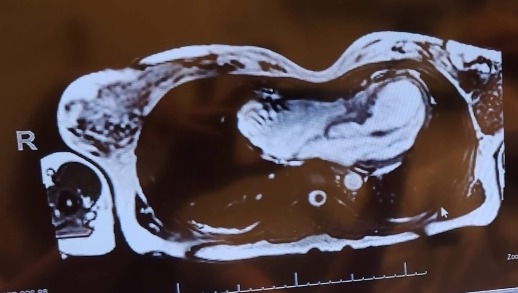

I will be out of work for at least 6 weeks while I recover from having a Nuss Procedure. I will need help covering bills and basic living expenses during that time.